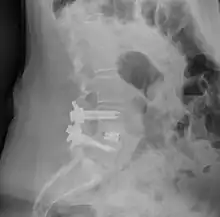

![]() Fusion of L5 and S1 | |